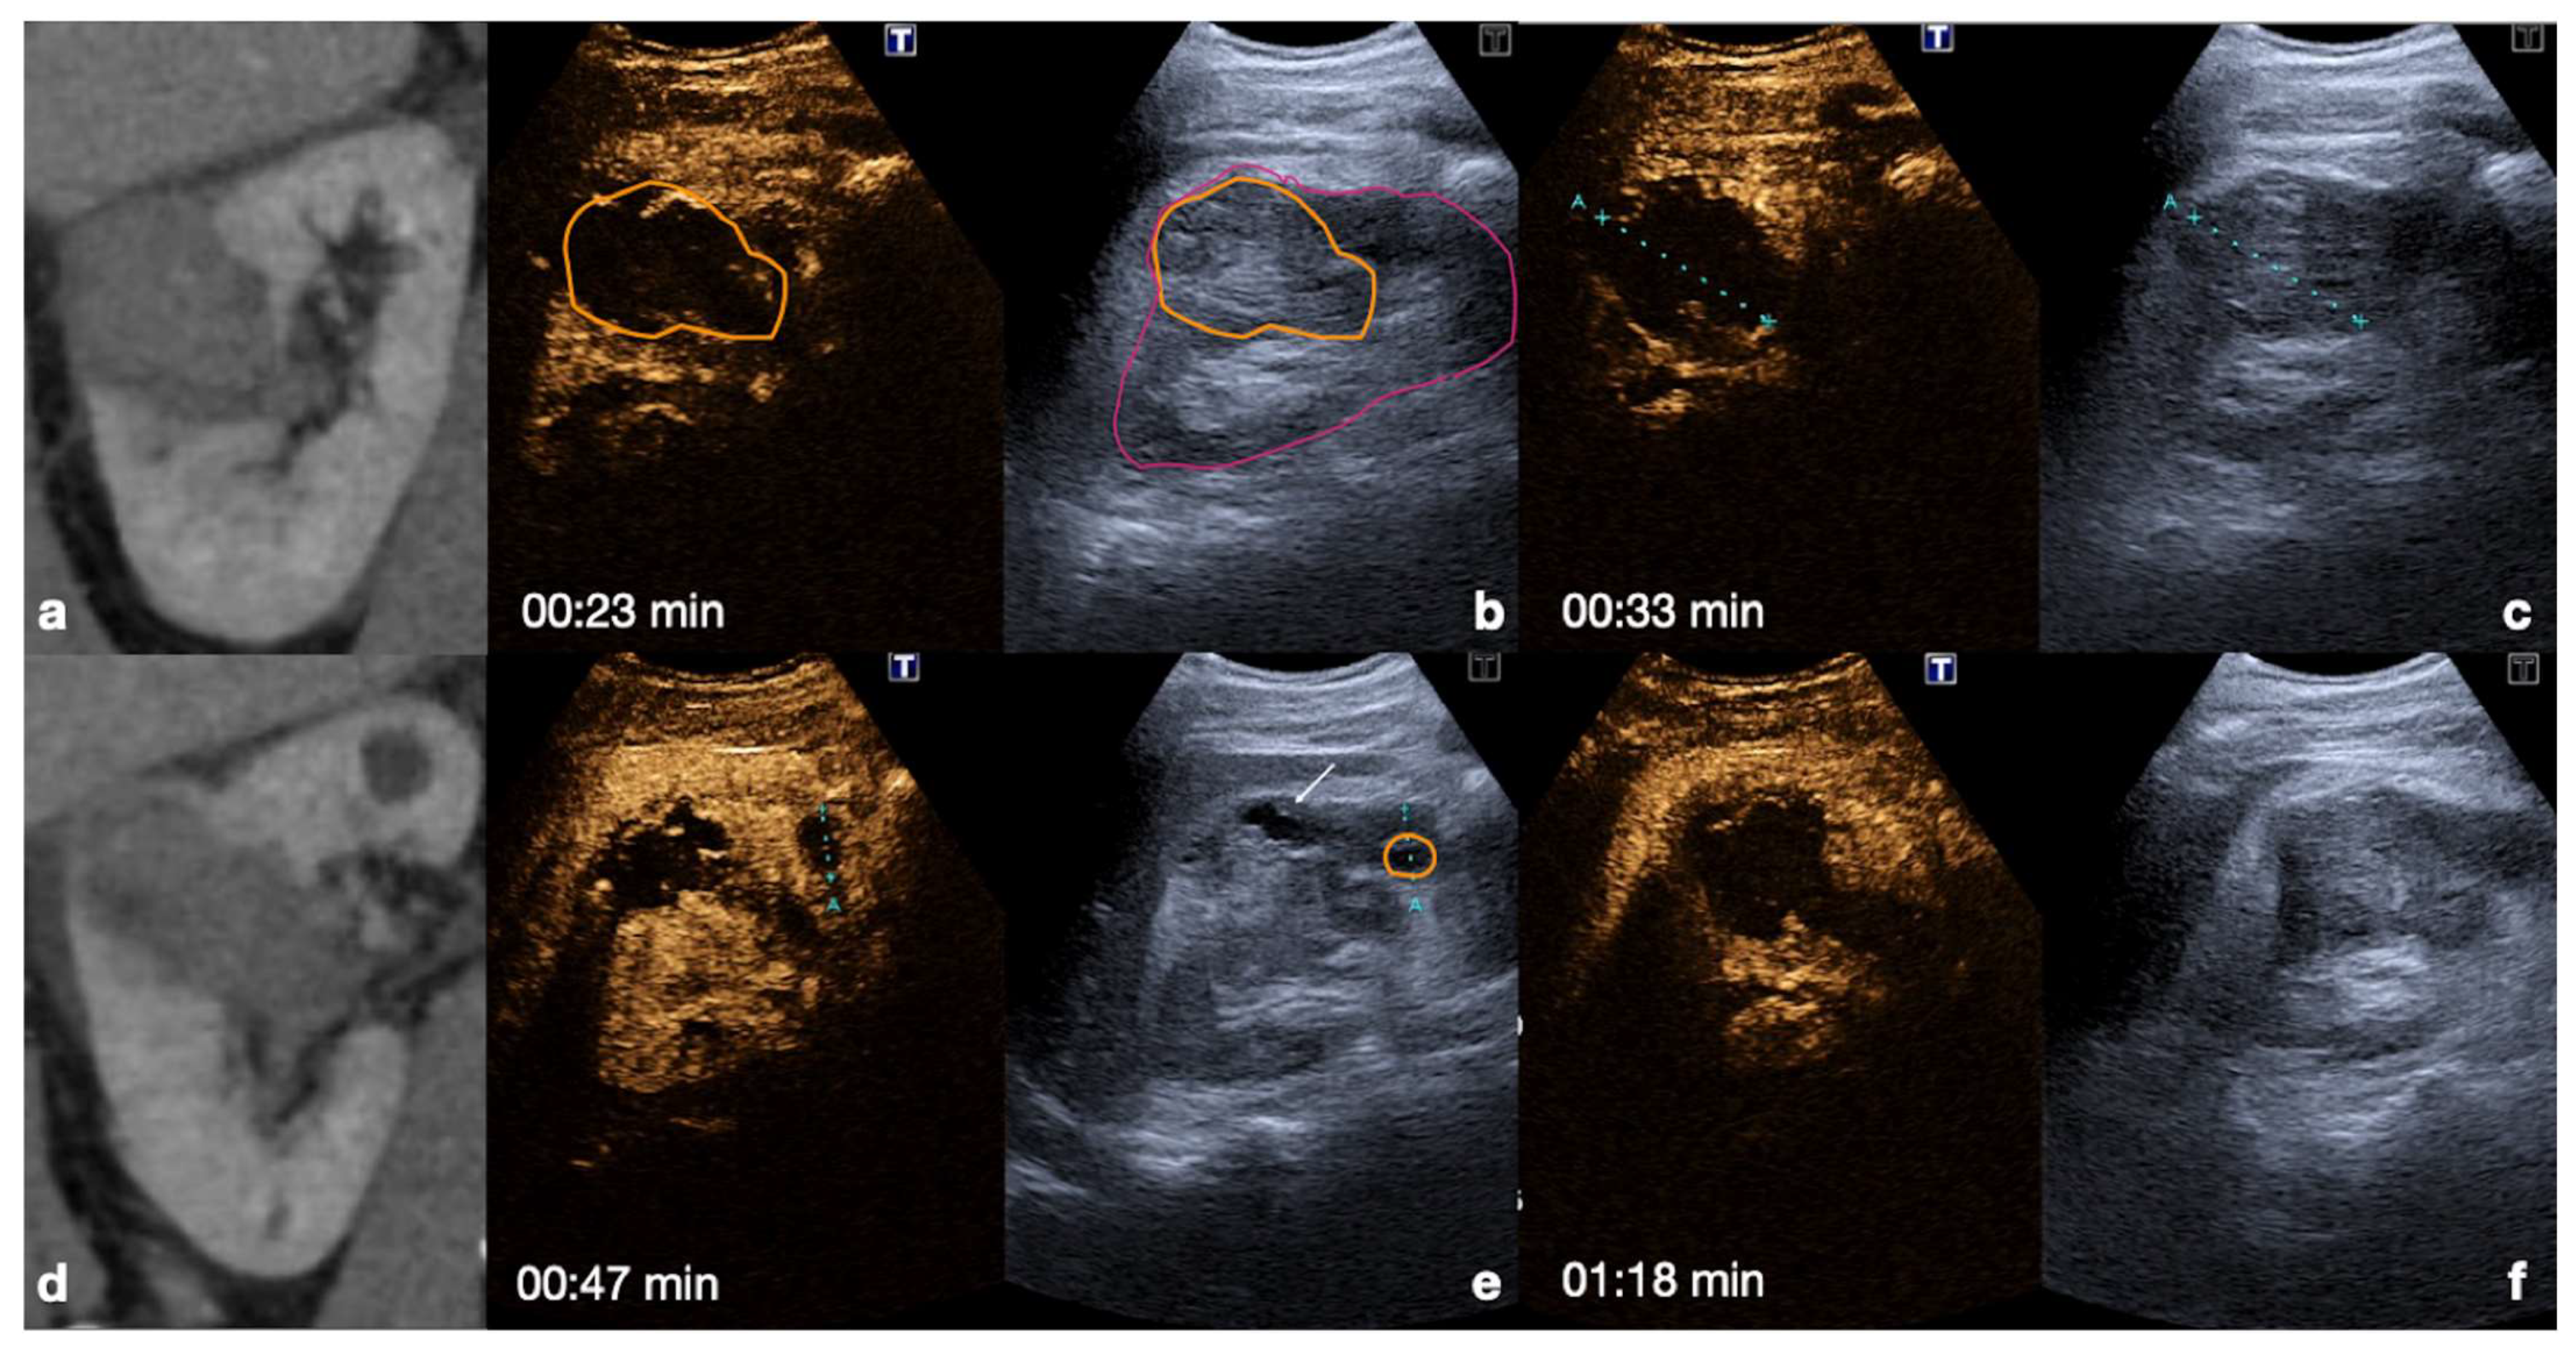

4.1. Step 1

4.2. Step 2

4.3. Step 3

4.4. Step 4

4.5. Step 5